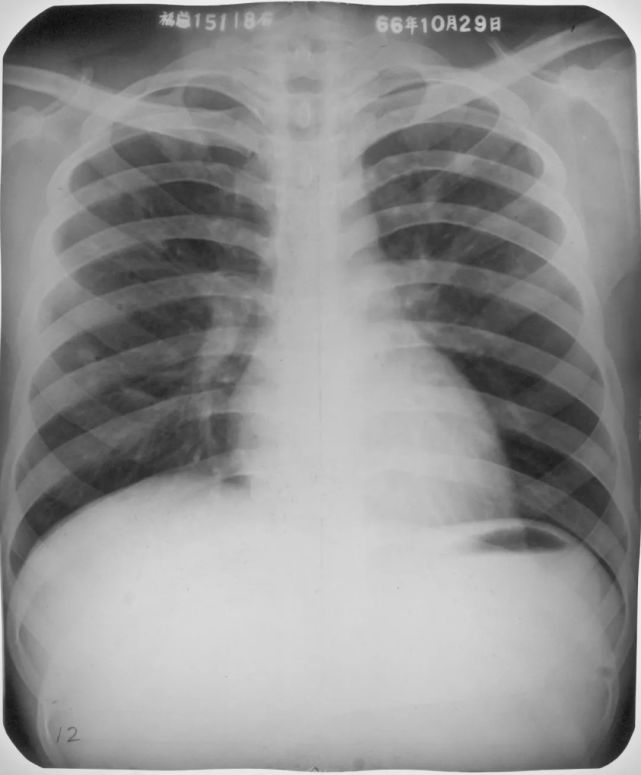

右肺下叶背段大叶性肺炎正侧位

图片

胸部正侧位片:右肺下叶背段见片状、三角形致密影,边缘模糊(箭头所指)